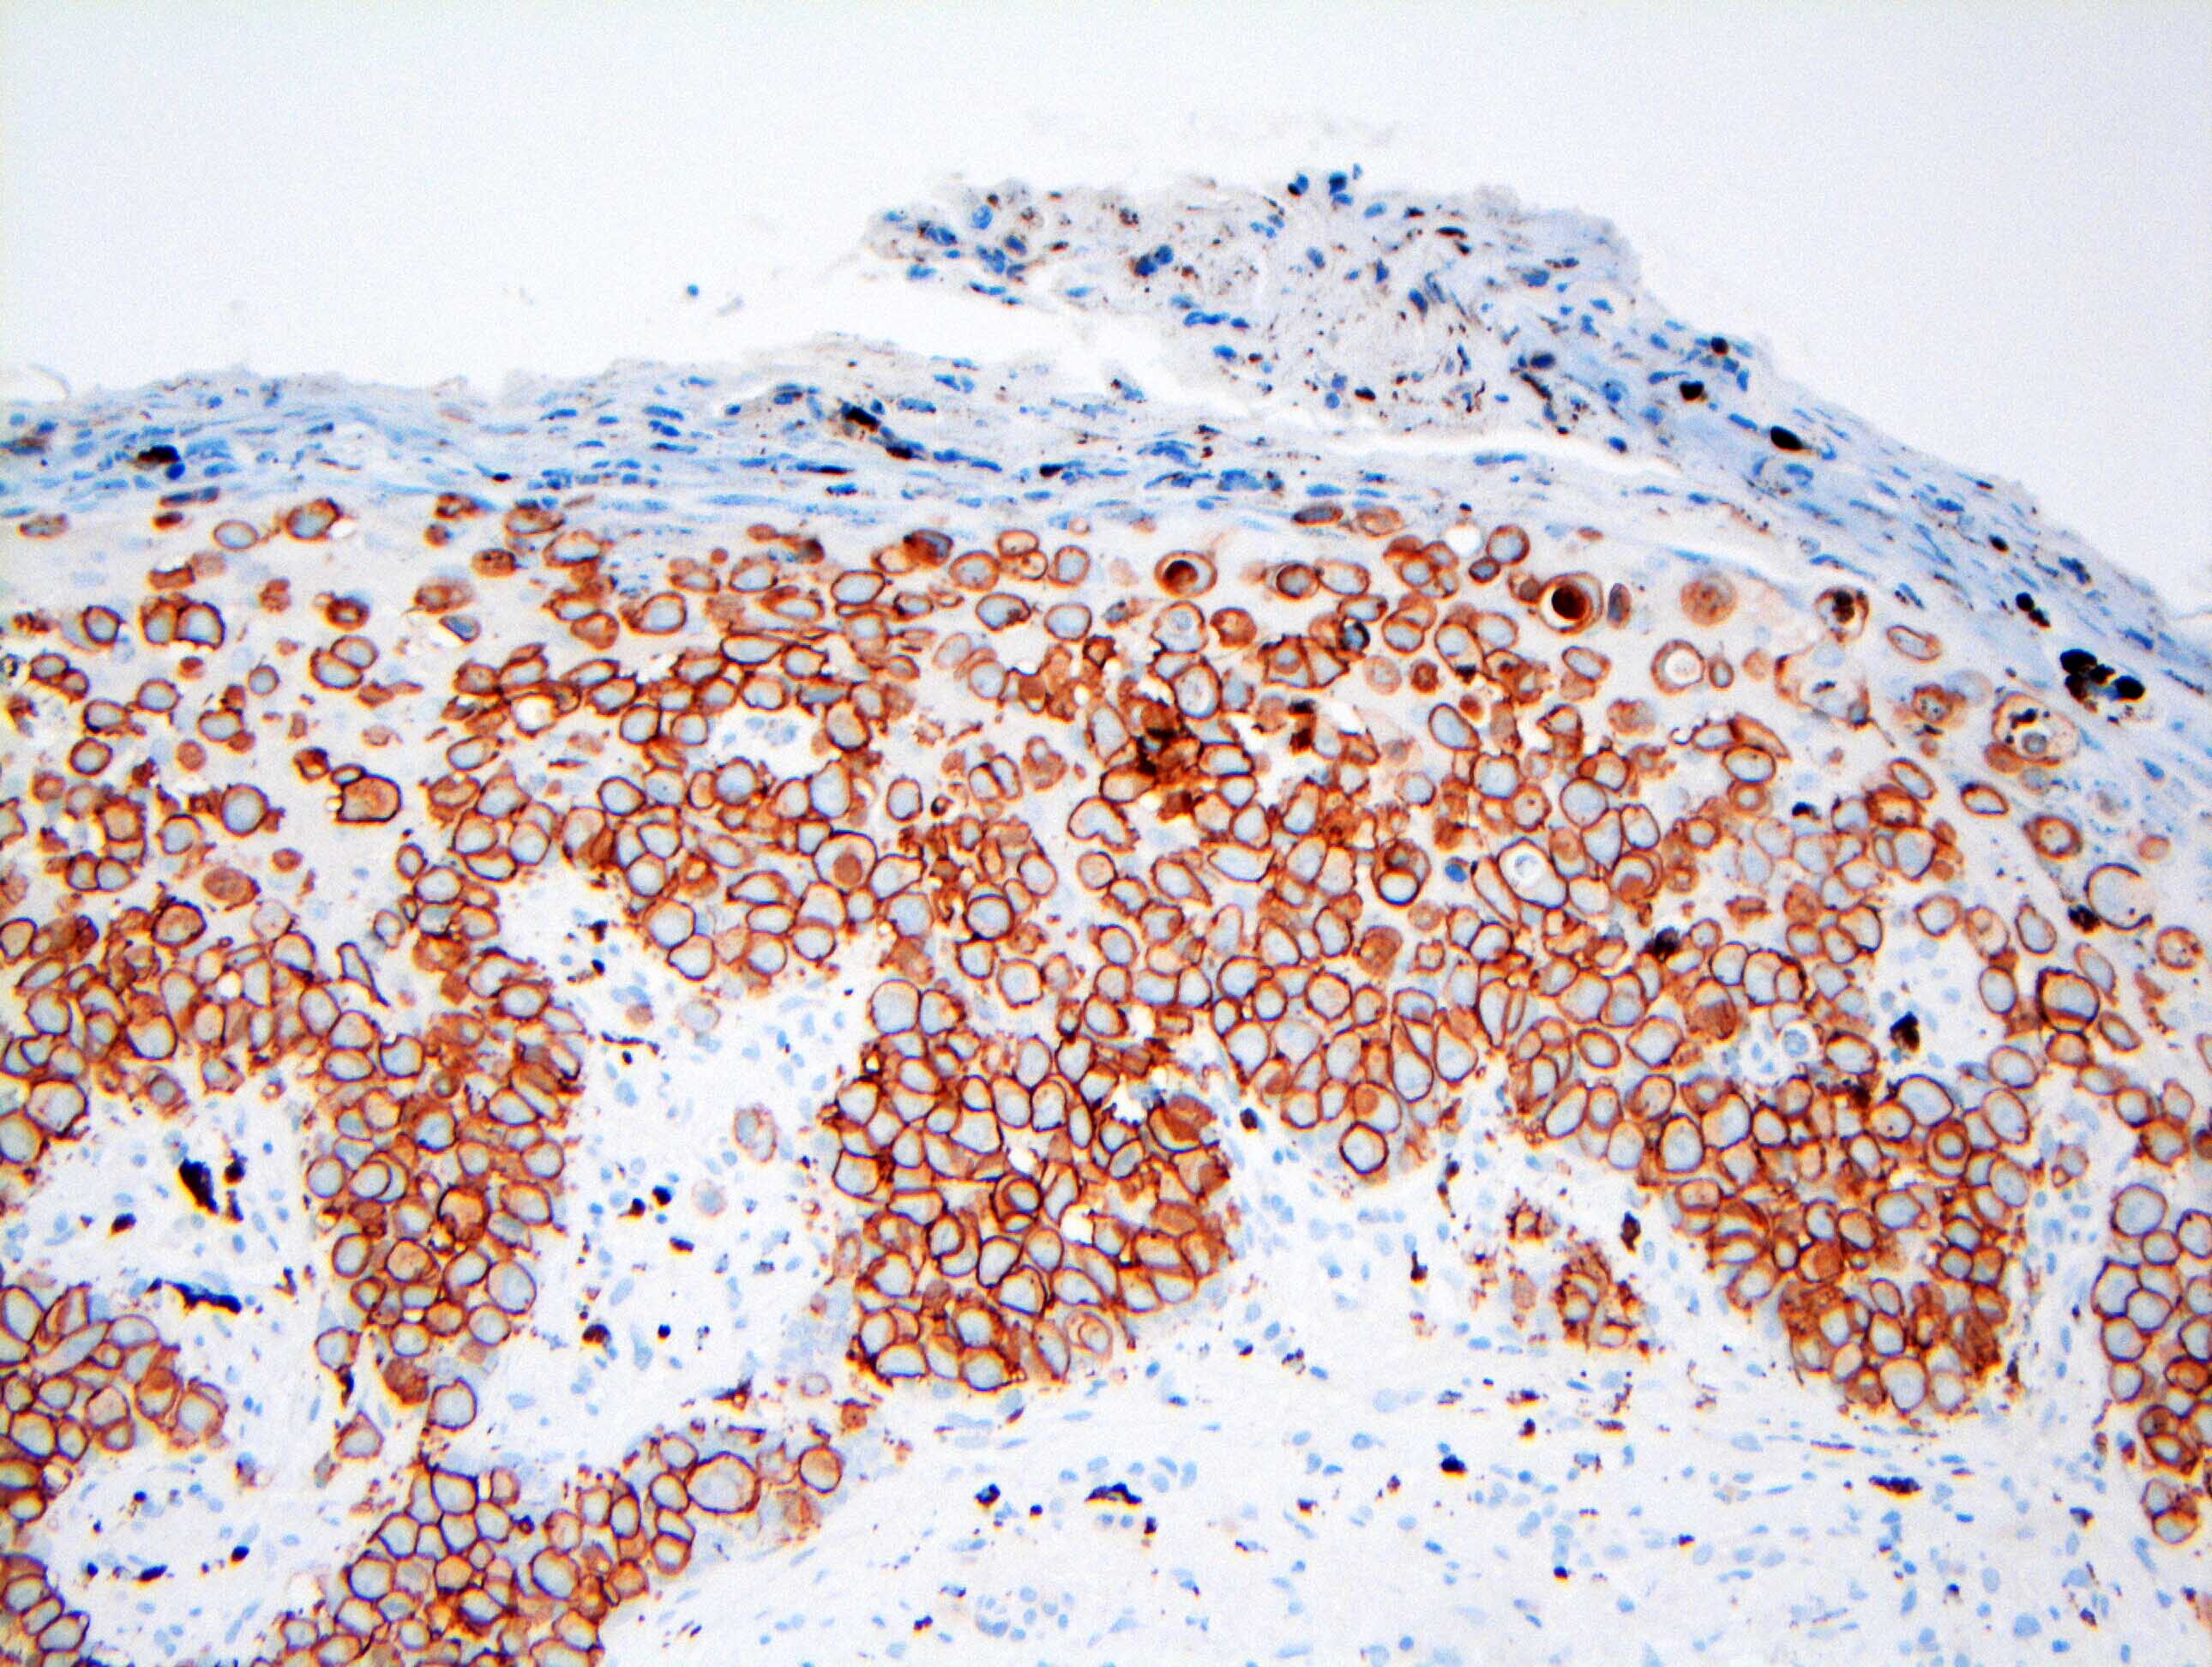

Microscopic (histologic) images

Contributed by Anna Biernacka, M.D., Ph.D. and Mary Ann Gimenez Sanders, M.D, Ph.D.

Positive stains

- CK7 (> 90%)

- HER2 (80 - 100%)

- CAM5.2 (70 - 100%)

- ER (10 - 40%)

- PR (0 - 30%) (Breast Cancer Res Treat 2013;141:1)

Negative stains

- HMB45 (<1%)

- MelanA (<1%)

- CK5/6 (0 - 2%)

- CK20 (0 - 1%)

- S100 (0 - 25%)

- Comment: The tumor cells are positive for CK7 and HER2 (3+) by immunohistochemistry, supporting the above diagnosis of Paget disease. ER and PR show no staining of in situ nuclei.